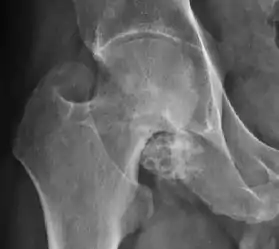

There are other pathological conditions that can affect the hip joint and radiographs help to make the appropriate diagnosis. Acute bacterial septic arthritis can be diagnosed by radiographs when a fast regional osteoporosis and destructive monoarticular process develops (Figure 1(f)). In case of tuberculous or brucella arthritis it is manifested as a slow progressive process, and diagnosis may be delayed.[1]

Synovial chondromatosis can be confidently diagnosed by X-ray when calcified cartilaginous chondromas are seen. However, other synovial proliferative processes, such as pigmented villonodular synovitis, require MRI for accurate diagnosis, although noncalcified synovitis can be suspected in radiographs by indirect signs, such as soft tissue swelling and/or erosions in the femoral head, femoral neck, or acetabulum (Figure 7).[1]

Figure 7:

Axial CT image of pigmented villonodular synovitis eroding the posterior cortex of the femoral neck.[1]

X-ray of synovial chondromatosis.[1]

CT of synovial chondromatosis.[1]